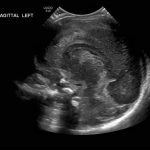

Age: 4 days (born at 24 weeks)

Sex: Male

Indication: Evaluate for germinal matrix hemorrhage

Grade 2 germinal matrix hemorrhage

Sample ReportLeft germinal matrix hemorrhage involving the caudothalamic groove and layering in the occipital horn of the left lateral ventricle without hydrocephalus (grade 2).

No abnormal brain parenchymal echogenicity or extra-axial collections.

Premature sulcation pattern.